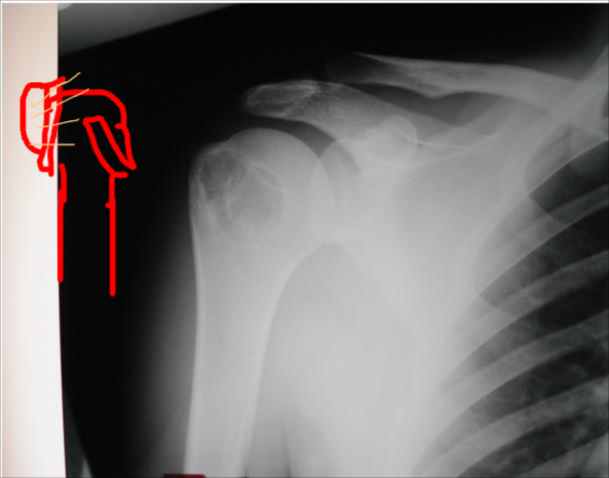

Osteoid Osteoma

Thick cortex